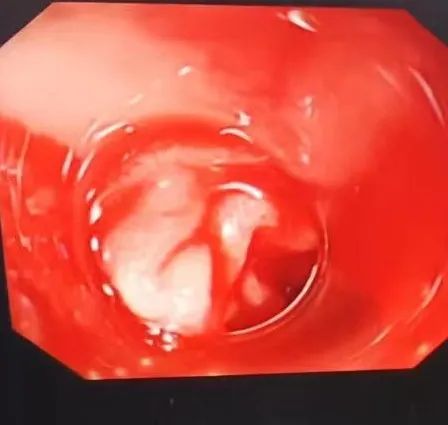

▲ 十二指肠血管残端活动性渗血

为了及时抢救患者生命,我院启动了上消化大出血急救绿色通道,各项检查优先完成。“失血性休克、消化道大出血诊断明确,需要快速施行床旁胃镜检查、治疗......”杜瑜第一时间明确诊断,征得家属充分理解和同意后,在杜瑜的指导下,陆崇锋副主任医师立即对病人进行了床旁胃镜检查,镜下可见患者球部有一直径约0.8*0.6cm溃疡灶,中央可见一血管残端,伴活动性出血,予和谐夹4枚夹闭血管残端,观察无继续出血,球后未见异常,患者出血终于停止。凌晨3点,经积极抑酸、补液、输血、纠正休克治疗后,患者生命体征逐渐平稳,一夜的抢救终于顺利结束了。由于抢救及时,黄伯各方面恢复顺利,复查胃镜溃疡面已愈合,很快康复出院。